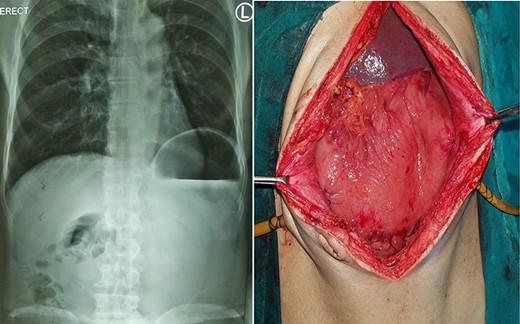

Chest X-ray and CT showing an elevated left hemi-diaphragm with a large sub-diaphragmatic air-fluid level.

A 19-year-old male with no known co-morbidities presented to the emergency department with 2-day history of severe upper abdominal pain and vomiting. He complained of similar episodes over the past 2 years, which used to get relieved spontaneously. On examination, the patient was tachycardic (110 bpm) with normal blood pressure and normothermic. The upper abdomen was asymmetrically distended, non-tender with a tympanic note. The laboratory investigations were within normal limits. Chest X-ray revealed markedly elevated (>4 cm) left hemi-diaphragm, huge gastric shadow with an air-fluid level and shift of mediastinum toward the right side (Fig. 1). Acute gastric volvulus was suspected based on the above finding, which was confirmed with contrast CT. Patient underwent initial laparoscopic evaluation, which was converted to open procedure. Intraoperatively, there was an organo-axial volvulus without any vascular compromise secondary to diaphragmatic eventration. It was de-rotated, decompressed and anterior abdominal wall suture gastropexy done. The freely mobile stomach was further reinforced with sham (trans-seromuscular) gastrojejunostomy. Left diaphragmatic eventration was plicated with polypropylene suture number 1 (Fig. 2) for which it required open conversion. Postoperative period was uneventful and discharged on Day 6. At 16-month follow-up, patient is doing absolutely fine.